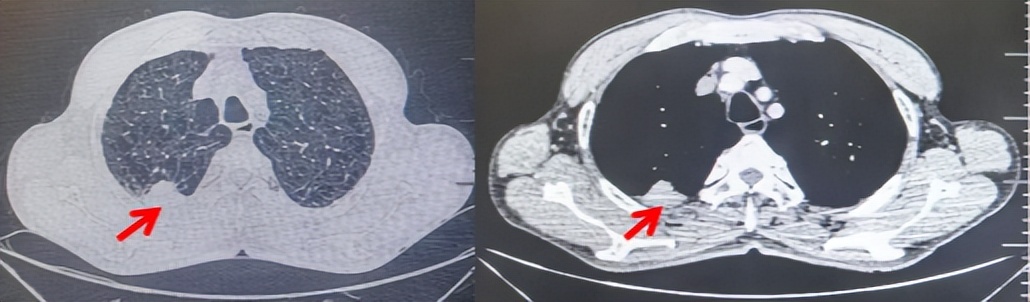

图5:患者手术前(2023.11)胸部CT肺窗及纵隔窗

图6:患者胸膜及纵隔转移(2024.09)胸部CT肺窗及纵隔窗